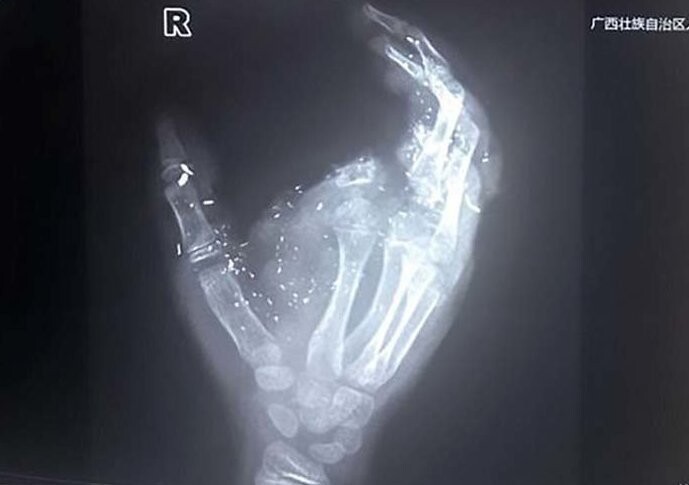

На рентгеновском снимке можно увидеть травмированную руку парня, ряд других фотографий демонстрирует, что после взрыва парень получил также много повреждений поменьше.

На рентгеновском снимке можно увидеть травмированную руку парня, ряд других фотографий демонстрирует, что после взрыва парень получил также много повреждений поменьше.